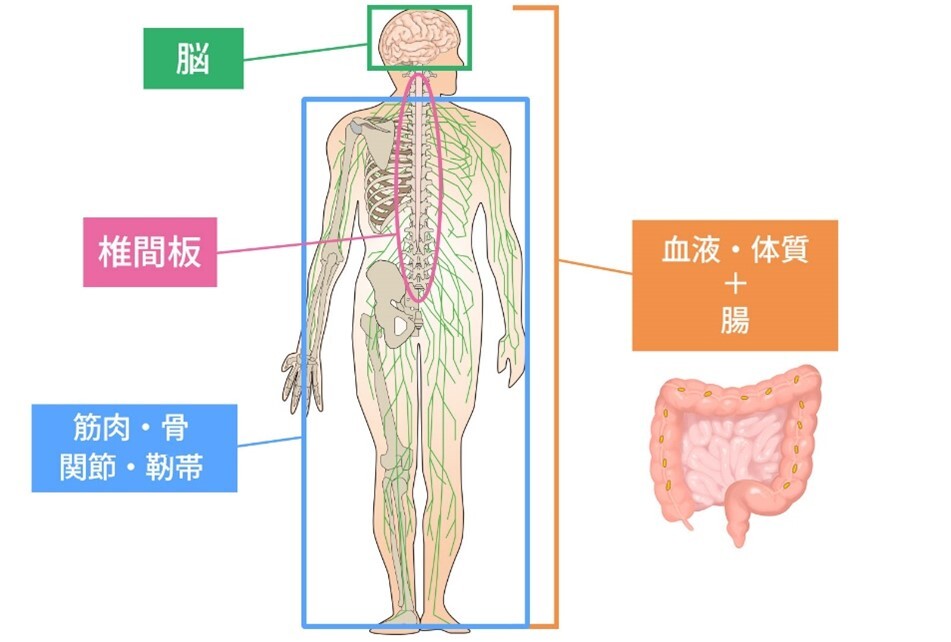

腰痛の要因はたくさんあり、その1つ1つの要因の強さは人それぞれ千差万別です。セルゲル法やフローレンス法は確かに腰痛の主要因である椎間板や脊柱管に対する治療のため高い効果が見込まれますが、人によっては椎間板や脊柱管以外の要素が強い方もいらっしゃいます。

そのような方も含めて我々は「腰痛の治療効果100%」を目指しており、この度、特別なプログラムを組んで実施するOJウェルネスセンターをオープンすることに致しました。

腰痛の4大要因について